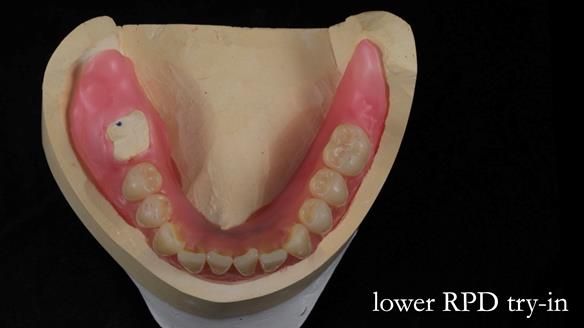

- Mk 1 lower immediate acrylic-based RPD

- Mk 2 lower metal-based RPD

The original plan was to finish the lower as a conventional metal-based partial denture, as shown in the initial design below.

However, once Rowan and I reviewed the remaining metal crown on tooth 46, we realised it would make an ideal abutment for a gasket denture. By reshaping the lingual surface of the crown, we created an excellent gasket seal.

This approach worked far better than the proposed ring-clasp design - improving retention, comfort, and aesthetics while keeping the design clean and simple.

Mary’s upper occlusal plane wasn’t parallel to her interpupillary line, and she specifically wanted that natural asymmetry preserved. Rowan arranged the teeth beautifully, following the exact contour and character of her original smile.

For both the upper and lower dentures, we used Schottlander Enigma Life teeth. I’ve been using these since 2014 and they’ve been outstanding - the surface texture, colour depth, and light reflection are superb. When arranged to mirror the patient’s natural tooth positions, they look completely lifelike.